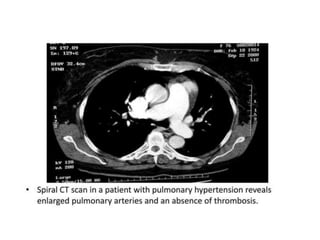

Pulmonary Artery Hypertension

 Findings in CT:

• Extra cardiac vascular signs:

• Enlarged pulmonary trunk >29 mm diameter is often

used as a general predictive cut-off

• Enlarged pulmonary arteries

• Mural calcification in central pulmonary arteries

• Evidence of previous pulmonary emboli